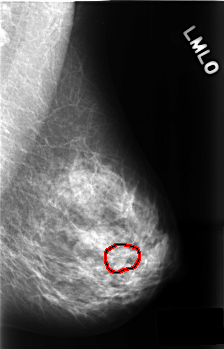

C_0468_1.LEFT_MLO

LEFT_MLO LINES 4536 PIXELS_PER_LINE 2912 BITS_PER_PIXEL 12 RESOLUTION 50 OVERLAY

FILE: C_0468_1.LEFT_MLO.OVERLAY

TOTAL_ABNORMALITIES 1

ABNORMALITY 1

LESION_TYPE MASS SHAPE OVAL MARGINS ILL_DEFINED

ASSESSMENT 3

SUBTLETY 5

PATHOLOGY BENIGN_WITHOUT_CALLBACK

TOTAL_OUTLINES 1

BOUNDARY